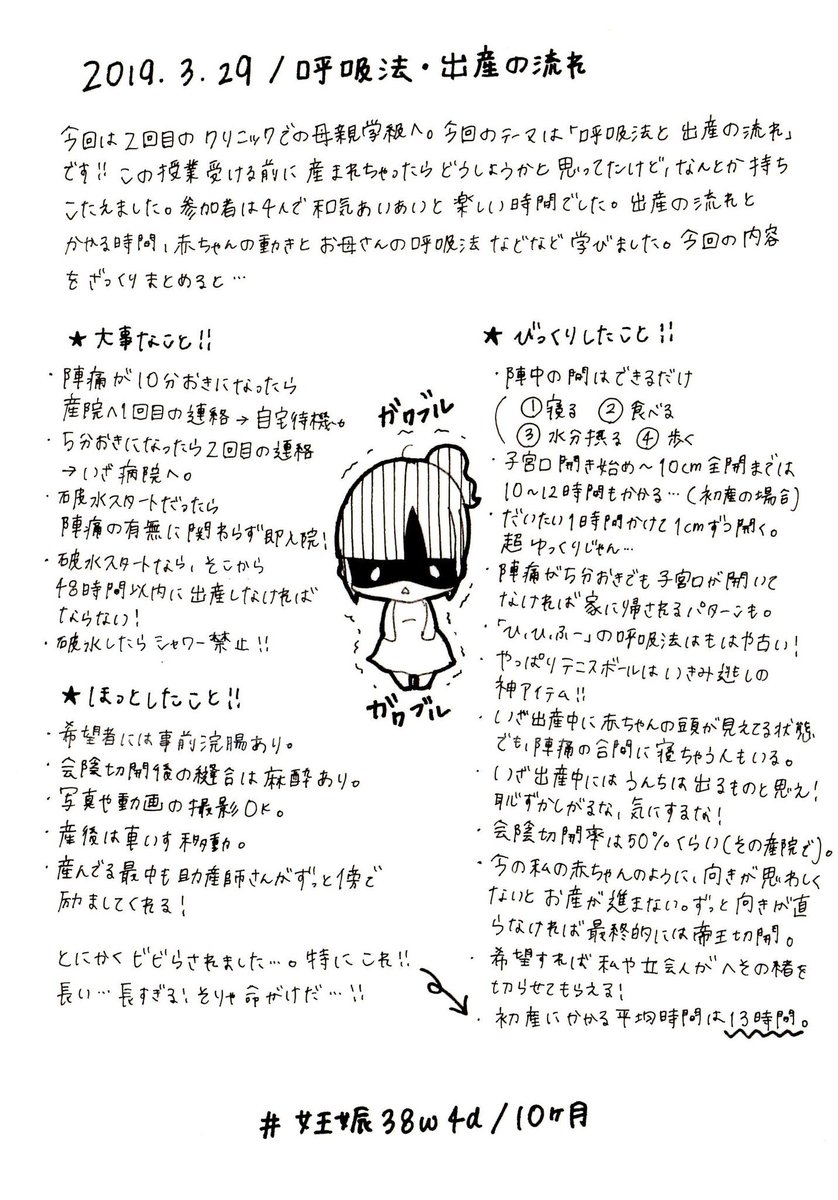

2019.3.29 2回目の産院での母親学級。 出産時の呼吸法や出産の流れを学び、いよいよ感がすごいです。とにかく子が産まれる前にこの授業受けられて良かった…! #育児漫画 #育児日記 #妊娠 #臨月 #妊娠10ヶ月 #正期産 #母親学級 #ママ垢さんと繋がりたい #オリジナル漫画 #絵描きさんと繫がりたい pic.twitter.com/VFenceIkl7

2019-09-07 12:45:42 拡大

拡大